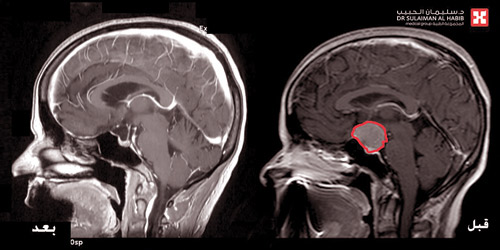

وقال إن الفحوصات التي أجريت للمريضة كشفت عن وجود ورم بقطر (3) سم متمركز في قاع الجمجمة بمنتصف الدماغ، ويضغط بشدة على عصبي البصر والغدة النخامية المسؤولة عن الهرمونات بالجسم. وقد قرر الفريق الطبي إجراء تدخل جراحي عاجل لاستئصال الورم. وذلك للحيلولة دون إصابة المريضة بمزيد من المضاعفات الخطيرة أبرزها فقدان البصر بشكل كامل، إضافة إلى ازدياد حدة الأعراض وحدوث خلل بهرمونات الجسم.

وقد أجريت للمريضة عملية جراحية دقيقة استغرقت 8 ساعات متواصلة تحت التخدير الكامل، باستخدام الميكروسكوب المتطور (Pentero)، وتم تحرير الورم من التصاقاته بالعصب البصري والغدة النخامية واستئصاله بالكامل.

وقد تكللت جهود الفريق الطبي بالنجاح ولله الحمد. وقد أبانت المؤشرات الحيوية للمريضة في الساعات الأولى بعد العملية تحسناً كبيراً في حالتها الصحية، واستكمل علاجها بإعطائها الأدوية اللازمة لضبط نسب الهرمونات بالجسم. وغادرت المريضة المستشفى في اليوم السابع بعد العملية، وقد انتهت معاناتها من الصداع المستمر وتحسنت لديها الرؤية.